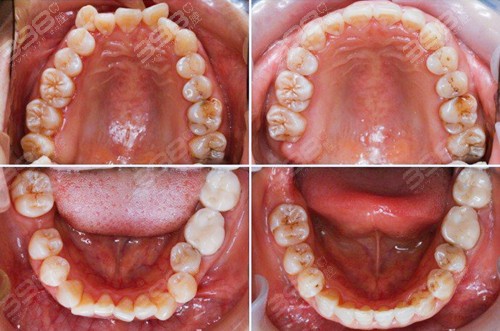

自锁托槽矫正是目前临床使用率很高的矫治器,大部分牙齿矫正患者已经开始摒弃传统托槽矫正器了,因为自锁托槽矫正比传统托槽矫正更加舒适,效率更高一些。

对美观度要求不高的患者,或者牙齿问题较大,隐形牙套不能快速解决问题的情况下,正畸医生还是会建议做自锁托槽矫正的。相对来说,陶瓷自锁托槽矫正的隐形比较好一些,笑起来只能露出一根细细的弓丝。

球面托槽正在被越来越多的医生和患者所选择,光滑面的托槽能够避免口腔溃疡的烦恼,这对正畸患者来说也是非常重要的哦!